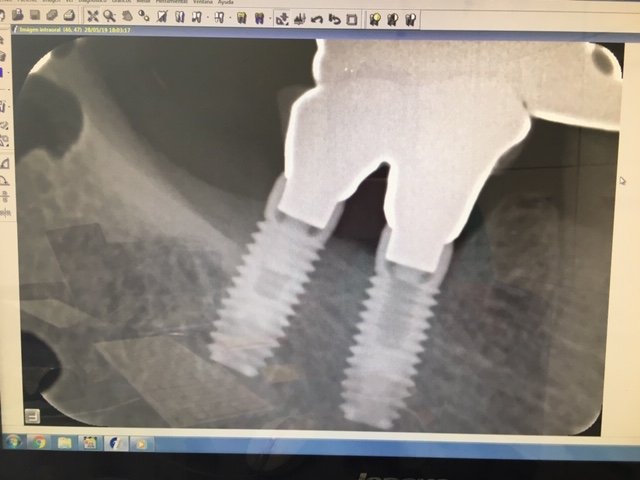

IMPLANTE EN 46 Y 47

PROTESIS CEMENTADA EN IMPLANTES 46 Y 47